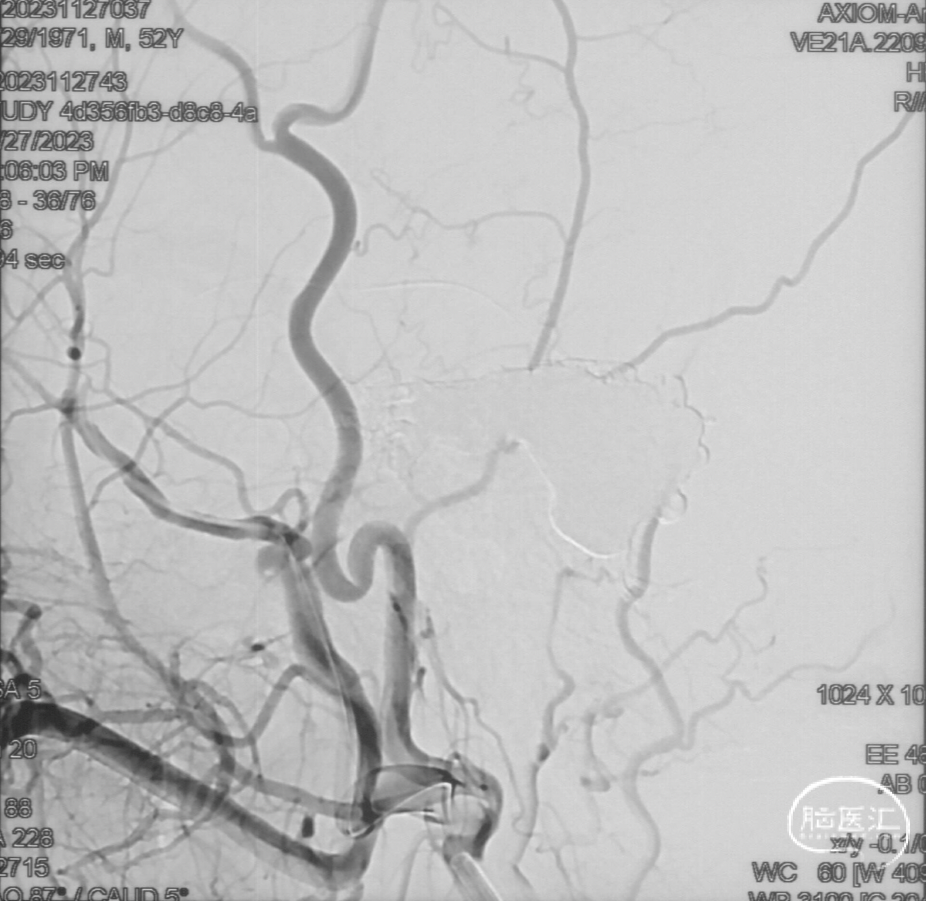

术前造影

证实为TDAVF,为岩上窦型。R-ECA正侧位见右侧脑膜中动脉分支、枕动脉分支、颞浅动脉分支向瘘口供血,经幕上迂曲扩张的静脉、中脑周围静脉、基底静脉向深部静脉引流。

R-ICA正侧位见右侧脑膜垂体干向瘘口供血

选取工作角度,正侧位造影